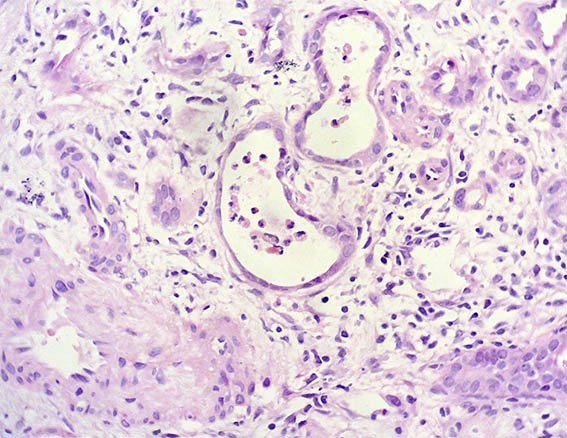

H&E, X400.

Figura 3.

Figura 4. H&E, X400.